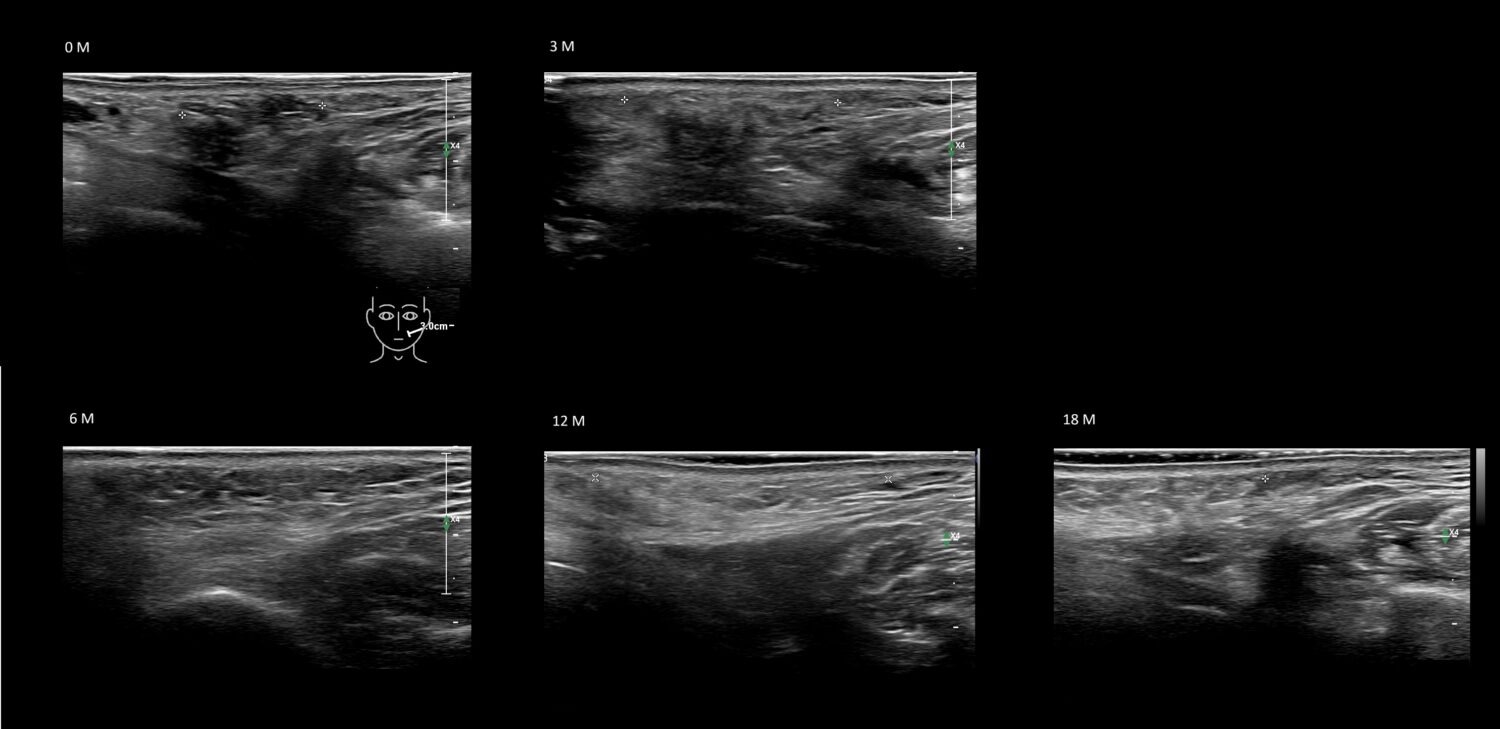

Fillers

Draw in the second image below where the fillers are located. To check if your answer is correct, swipe the first image to the right.